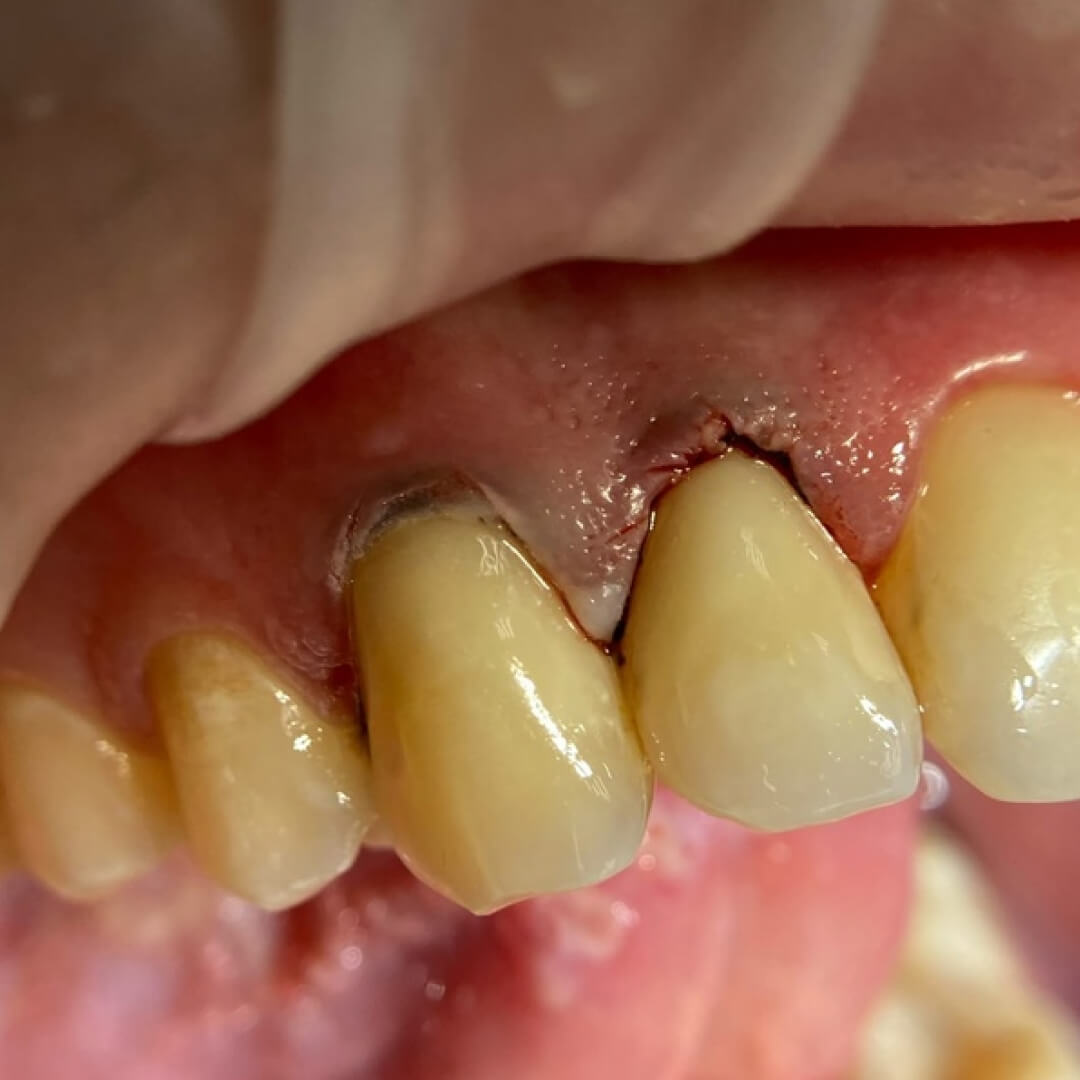

До и после лечения

Пациентка обратилась в «Стоматологию Комфорта» с жалобами на эстетический дефект передних зубов. Врач Галухина Карина Николаевна во время осмотра выявила кариозные полости на 1.2. и 1.3 зубах. Было решено провести лечение с помощью пломбировочного материала Vitremer A3. Врач также рекомендовала рациональную гигиену полости рта после лечения.

- пломбирование композитом Vitremer;

- шлифовка и полировка пломбы;

- обработка полости рта.